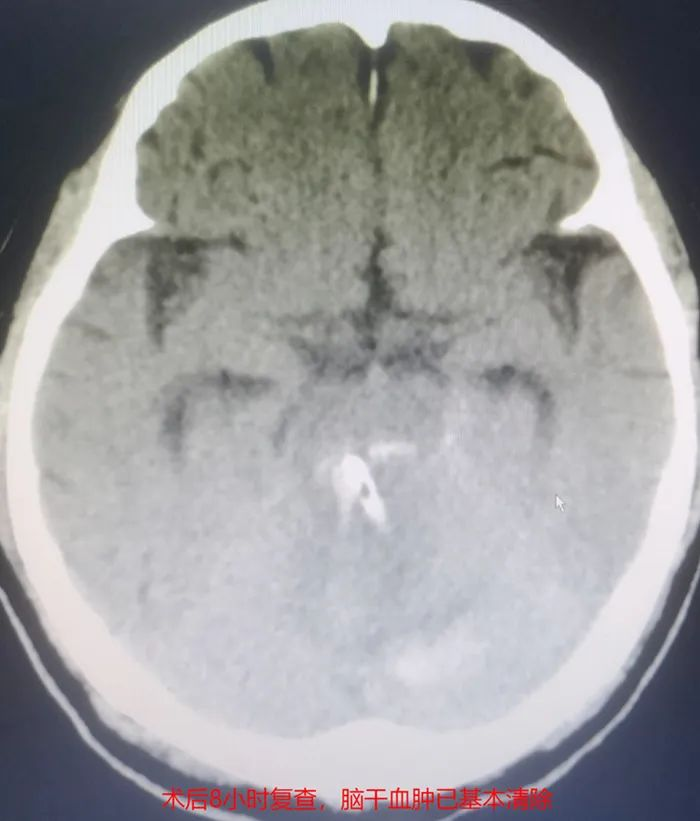

▲患者术后影像

术后8小时复查颅脑CT示引流管位置精准、脑干血肿基本清除,48小时内成功拔管。